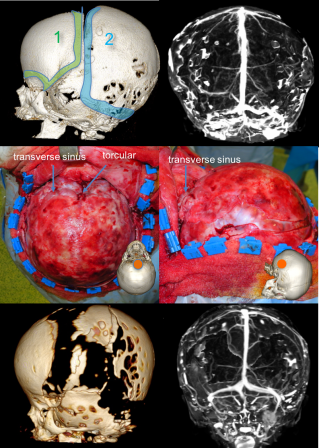

la craniectomie péri-occipitale

elle est indiquée en première ou en seconde intention en fonction de la présentation clinique et radiologique. elle permet de lever la compression du carrefour veineux dural qui est à l’origine de l’hydrocéphalie et de l’hypertension intra-crânienne.

craniectomie à la gouge sous contrôle visuel pour ne pas léser la dure-mère- dégagement des sinus transverses et du torcular

résultats

- l’imagerie montrant la correction

- de l’hydrocéphalie

- de la compression des sillons arachnoïdiens

- de l’engagement tonsillaire

- l’amélioration morphologique avec galbe frontal restauré